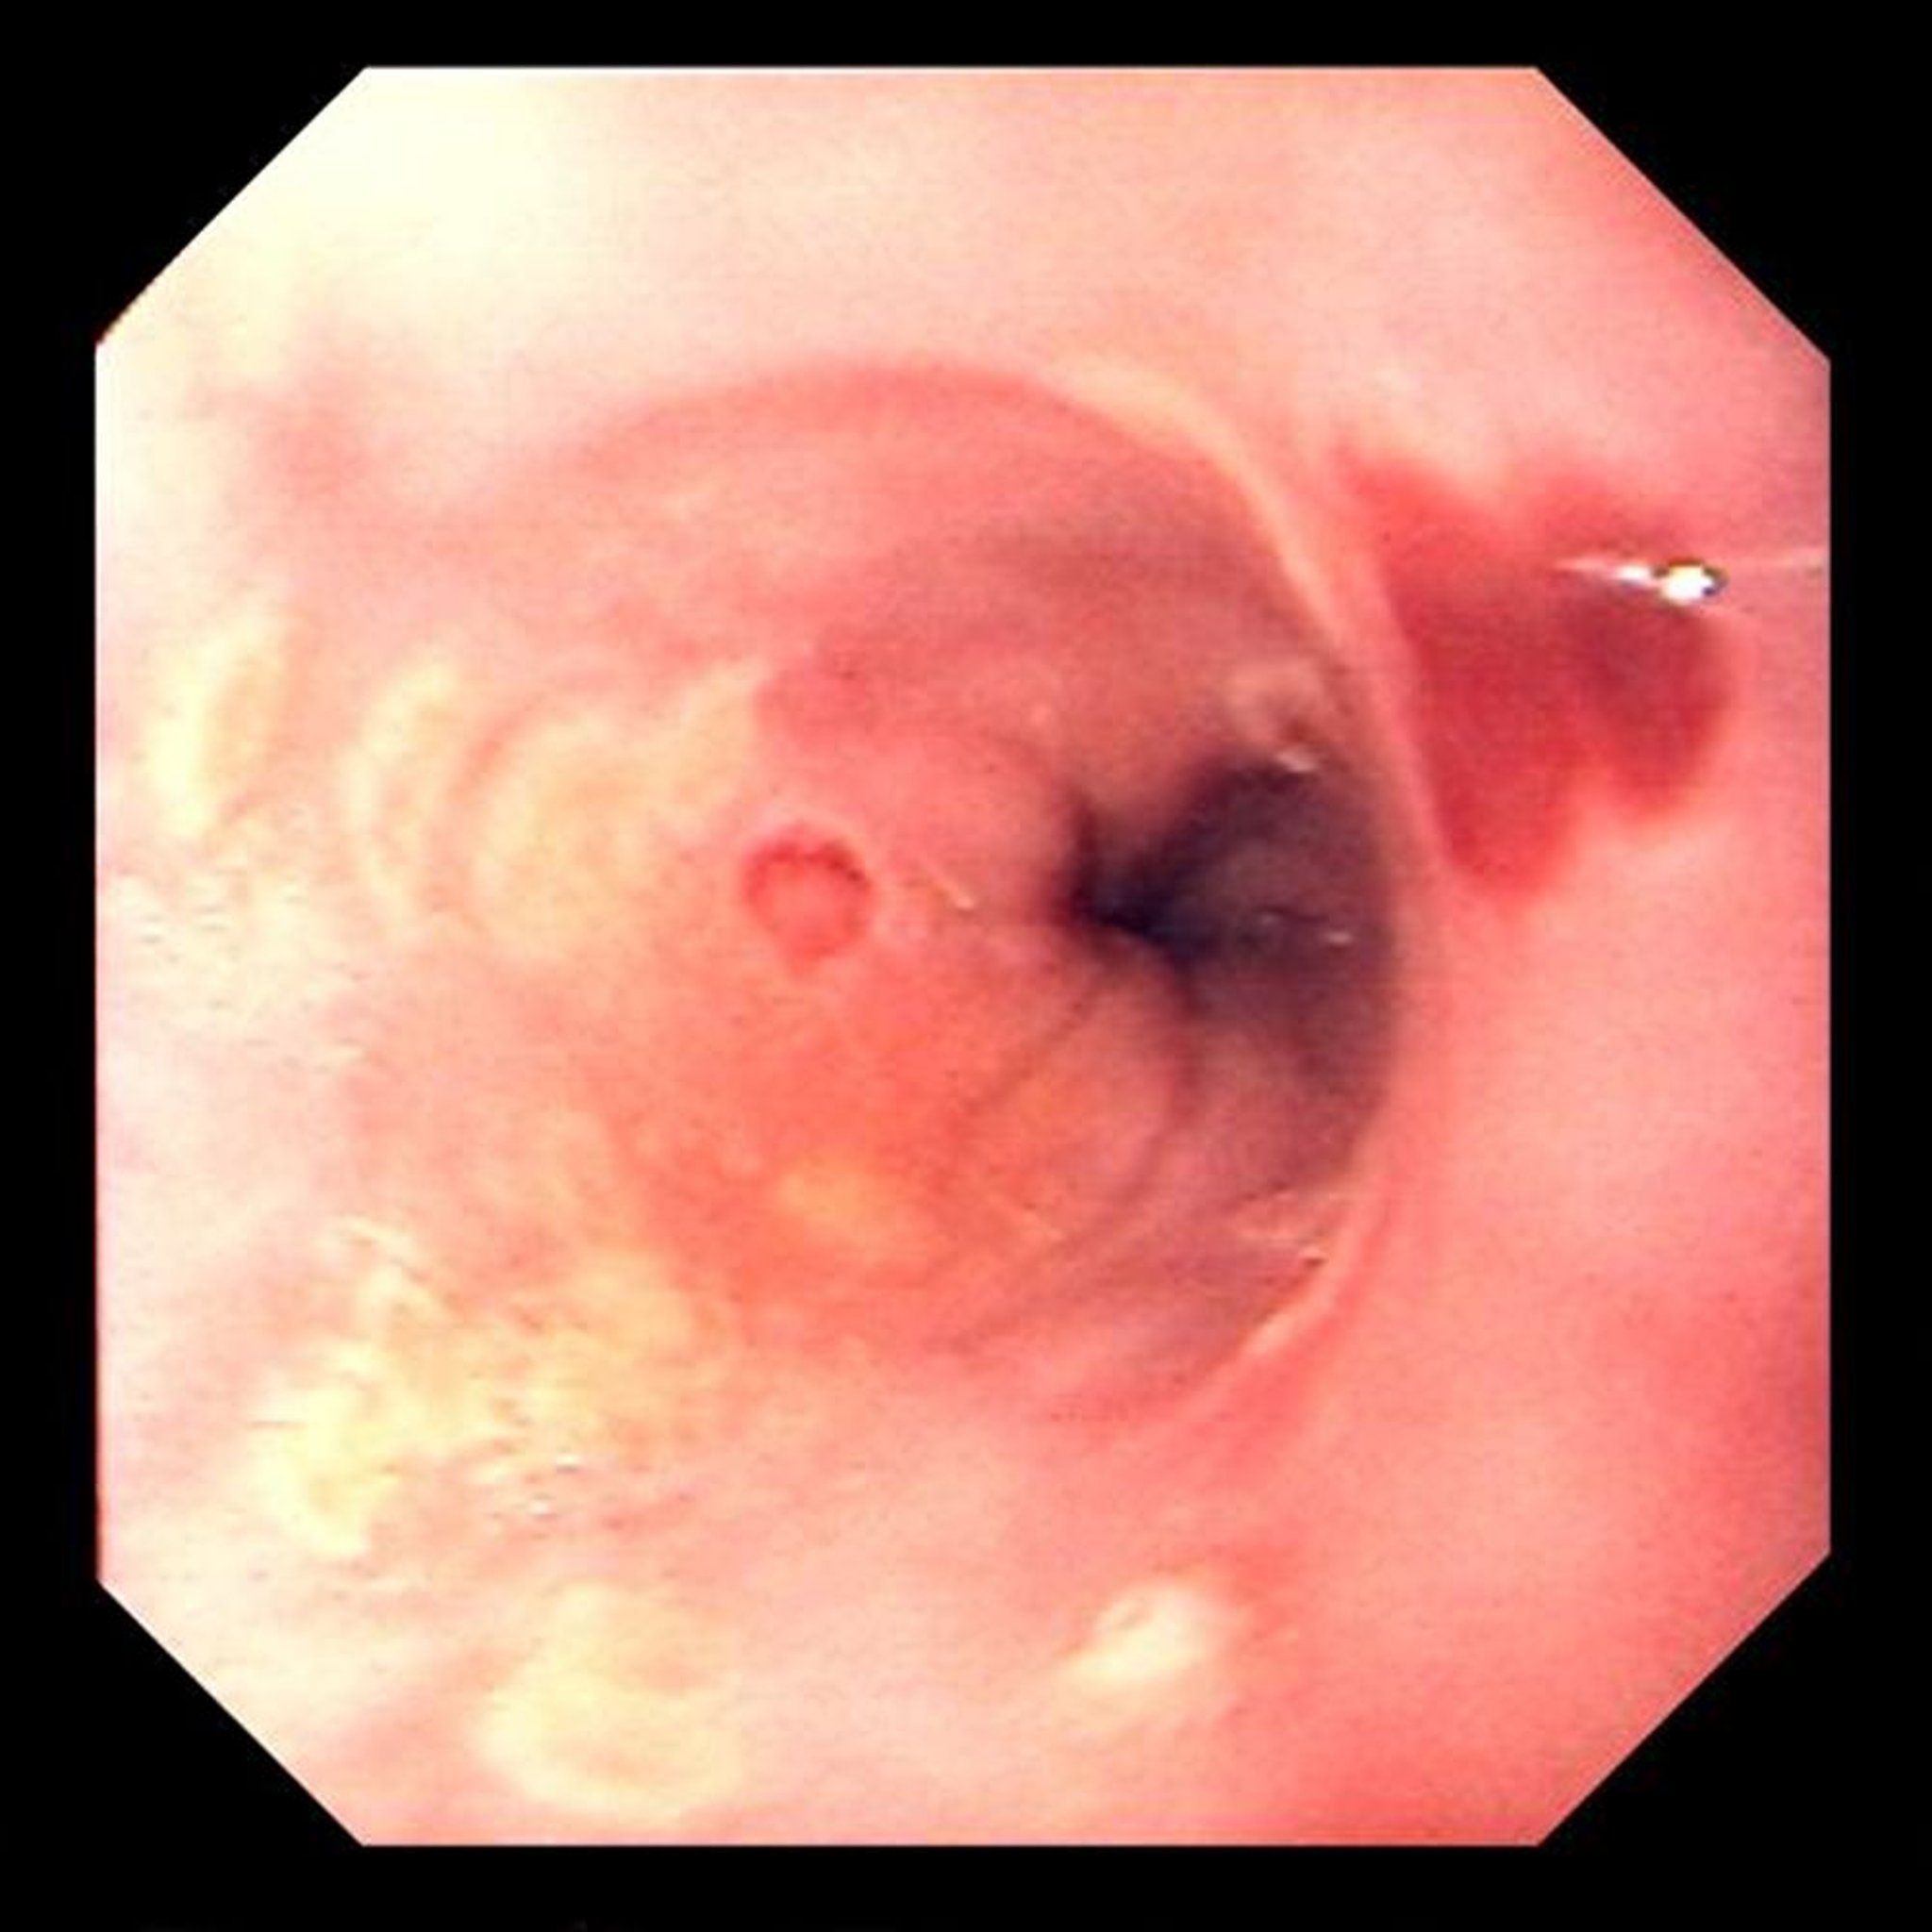

Herpes-simplex-Ösophagitis

Fokale Ulzerationen sind typisch für Herpes-simplex-Virus-Ösophagitis.

Image provided by David M. Martin, MD.